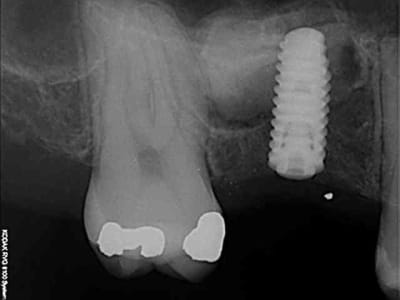

pour votre plaisir mon ami 8 mois d'écarts

fenêtre fermée par du vitalos pas de membrane technique "grosse ouverture"

ce qui ne me plait pas dans ton cas pxav c'est que tu n'as pas décollé la paroi médiale du sinus, tu fais une grosse fenêtre du coup tu te prives d'un apport vasculaire non négligeable.

la demande était radio à J et J+6 mois, pas "présentez un cas de comblement de sinus parfait".

Perso je trouve le résultat "correct" imagine si en plus j'avais fais un CS nickel...

j'ai une préférence pour le mode "ogival" plutôt que "mis à plat", pour des raisons mécaniques, (il me semble que le résultat est meilleur) mais j'ai peut etre tord.

Par contre, l'ouverture réduite ne me gêne pas au contraire, mais dans ce cas là le choix était large.